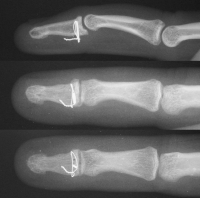

| Case 1. This patient sustained a closed comminuted fracture of the distal phalanx with dorsal-palmar split of the base and a completely displaced transverse fracture of the diaphysis. |

| Inury. |

| One week postop. |

| Three months postop, after removal of prominent pins in the office. |